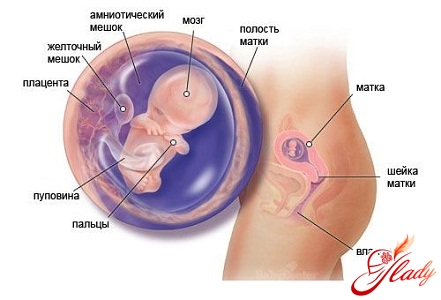

Беременность 10 неделя: признаки. Этот этап беременности считается заключительным в стадии эмбриона. К 10 недели беременности уже заложены все параметры тела, теперь в последующие 6,5 месяцев предстоит завершение «строительства» вашего малыша. Теперь, когда хвостика уже нет, он становится все больше похож сам на себя: пальчики уже обособлены, появляются зубные зачатки и вкусовой сосочек языка, сердце уже полностью сформировано, с космической скоростью продолжает развиваться мозг. Хотя наружные гениталии на 10 неделе еще неопределенны, яички мальчиков уже начинают вырабатывать тестостерон (мужской гормон).

Беременность 10 неделя: узи. На этом сроке беременности малыш входит в фетальный период своего развития. Теперь эмбрион уже можно официально называть плодом. Если до десяти недель с эмбрионом все было в порядке, ему уже практически не грозят никакие врожденные аномалии. На данном этапе своего развития он уже имеет огромное количество достижений! К этому моменту он уже способен хотя и непроизвольно, но самостоятельно двигаться, у него уже есть ручки, ножки, сформированы локтевые суставы, верхняя губа, ушные раковины и пальчики (как на руках, так и ногах), начали формироваться коленки. Также в этот период идет развитие молочных зубов и начинает образовываться диафрагма. Плод чувствует себя комфортно внутри плодного пузыря, заполненного околоплодными водами (амниотической жидкостью).

Если у вас беременность 10 неделя, то ваш малыш подрос до размера крупной сливы. Обычно на таком сроке беременности длина плода составляет от 31 до 42 мм, а вес — около 5 грамм.